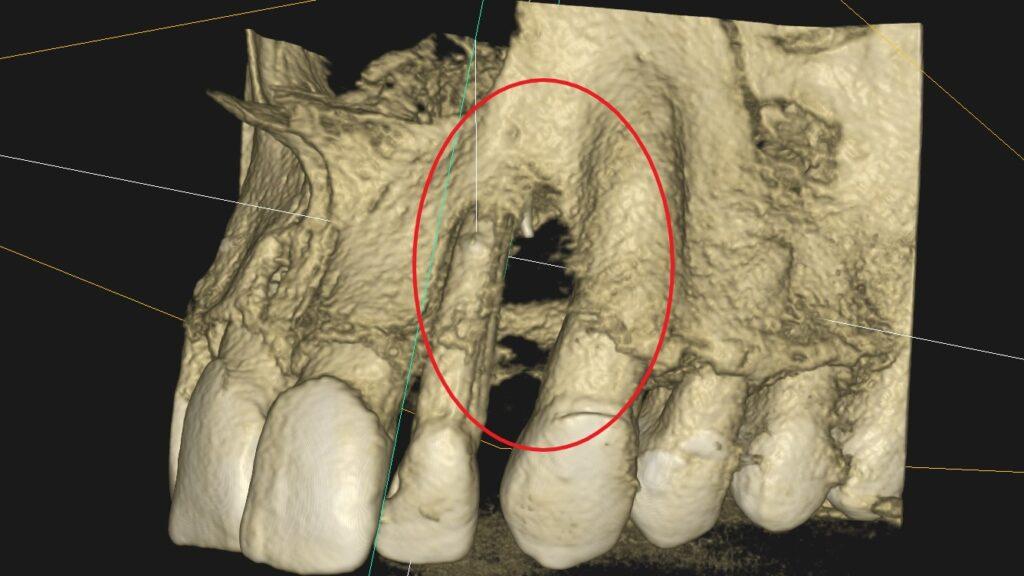

Leczenie kanałowe jest leczeniem skutecznym. Prawidłowe leczenie kanałowe sprawia, że ząb przestaje być ogniskiem zakażenia, a tkanki wokół goją się. Wyleczenie zęba powoduje, że przyczyna choroby tkanek około zębowych [na RTG widzimy jedynie chorobę kości] zostaje usunięta. Eliminacja przyczyny choroby umożliwia gojenie się zmian chorobowych.

Na poniższych zdjęciach RTG – WIDAĆ GOJENIE ZMIAN ZAPALNYCH KOŚCI.

Nie jest prawdą, że leczenie kanałowe w każdym przypadku jest szkodliwe. Ogniskami zakażenia są zęby martwe, nieprzeleczone kanałowo, zęby z nieprawidłowym leczeniem kanałowym i to właśnie one są zagrożeniem i powinny być eliminowane.